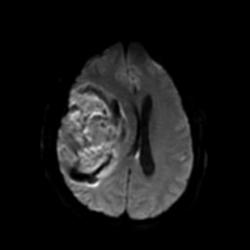

В продолжение темы нарушений мозгового кровообращения публикую случай геморрагического инсульта.

Пациент 65 лет. Заболел остро 4 часа назад. На обследование доставлен в состоянии угнетенного сознания.

Наличие крови наиболее четко видно на T2* GRE импульсной последовательности.

Наличие крови наиболее четко видно на T2* GRE импульсной последовательности.

А каковы признаки, позволяющие сказать, что это именной кровь, а не опухоль, например?

А я бы вобще сказал, что это объёмное образование с кровоизлиянием в строму образования

magnetom, абсолютно закономерное предположение!

Чисто теоретически сверхострую гематому сложно отличить от опухоли. Давайте разбираться: эритроциты, только что вышедшие за пределы сосуда (артерии), содержат полностью оксигенированный гемоглобин и другие комоненты крови. Оксигемоглобин имеет диамагнитные свойства и будет давать умеренно гипоинтенсивный сигнал при T1 ВИ и слабогиперинтенсивный сигнал на T2 ВИ. Такую же интенсивность МР сигнала могут давать и некоторые опухоли.

Гематому в данном случае с головой выдает периферическая полоска, окружающая образование с гипоинтенсивным (особенно на GRE ИП) МР сигналом. Иначе чем еще ее можно объяснить?

К тому же, есть клинические данные: за 4 часа до исследования пациент на фоне головной боли внезапно потерял сознание. Привезли его уже в коме. Не мог бы человек с опухолью такого размера с височно-тенториальным вклинением и грубым вклинением под серп чувствовать себя нормально.